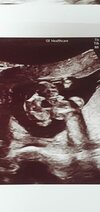

Witajcie mam pytanie odnośnie usg nie ukrywam że liczę na dziewczynkę ale najważniejsze żeby zdrowe było. Lekarz jakiś tępy i nic nie powiedział o tym a ja oszaleje. Chodzi o te usg u góry dziękuję za odpowiedź

Załączniki

• IMG_20190828_115656_01.jpg

IMG_20190828_115656_01.jpg

91,2 KB · Wyświetleń: 20 197